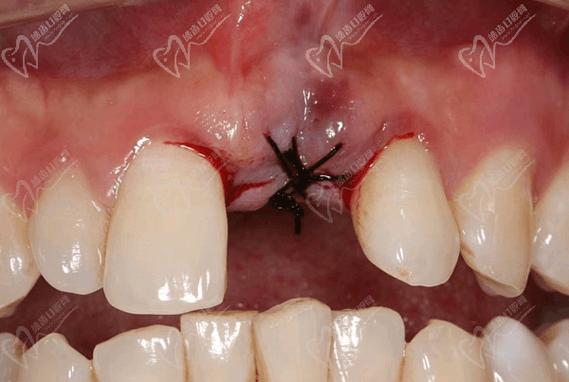

(图片来源网络,侵删) -